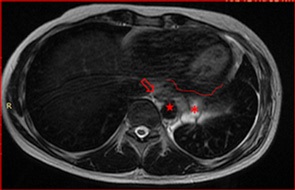

Right after the chemotherapy, he also received Stereotactic Body Radiation Therapy (SBRT) - 35 Grays in 5 sessions in June, 2021), as well as, to decrease the likelihood of disease increment. In vain, so the persistence of disease in contact with the pericardium, as showed in Figure 3, would progress shortly

The patient presented with voluminous and symptomatic disease less than six months of chemotherapy end and less than two months of radiotherapy. He restarted with pain in left hemithorax, cough, shortness of breath, lack of appetite and daily vespertine fever. MRI scans in August, 2021 showed new lesions on pleural surfaces beyond the residual mass previously seen (Figures 4a, 4b and 4c). One of the lesions, on the extra-pleural fat adjacent to the diaphragm, extended inferiorly, pushing downward the muscle.